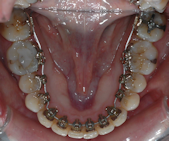

Il existe diverses possibilités de technique collée, externe , interne Les brackets métalliques peuvent être remplacés dans un souci d'esthétique par des éléments transparents ou de la couleur des dents.

Les techniques linguales offrent la possibilité d’un appareil orthodontique efficace et totalement invisible.